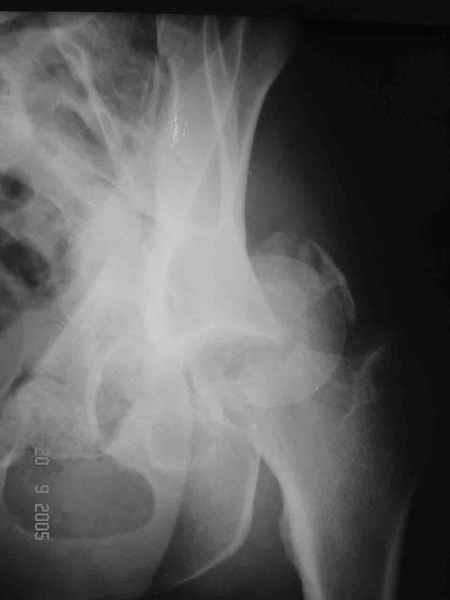

Больной 18 мая 2003 года в автоаварии получил перелом левой вертлужной впадины, вывих бедра. Госпитализирован в один из стационаров области.Вывих вправлен. В последствии бедро вывихивалось еще дважды. На консультацию был представлен снимок от 19.05.03г., больной переведен к нам 3.06.03г. Снимок при поступлении - перелом впадины, задне-верхний вывих бедра. 05.06.2003 г. выполнено открытое вправление вывиха левого бедра и остеосинтез стенки вертлужной впадины двумя винтами. Послеоперационный период без осложнений. Объем движений в левом тазобедренном суставе восстановился полностью. Выписан на амбулаторное лечение в удовлетворительном состоянии с рекомендациями 3 месяца ходить на костылях без нагрузки на оперированную конечность. На контрольных рентгенограммах левого тазобедренного сустава 13.10.2003 г. - признаки консолидации перелома; плотность, форма головки и состояние суставных поверхностей удовлетворительные. Разрешена дозированная осевая нагрузка, на конечность с использованием дополнительной опоры. 19.12.2003 г. больной обратился с жалобами на боли в левом тазобедренном суставе. На рентгенограммах левого тазобедренного сустава 19.12.2003 г., 20.02.04г. - асептичекий некроз головки бедра. 5.04.04г. - эндопротез. Сейчас ходит без трости, не хромает. Особенность эндопротезирования - при удалении винтов прослежена линия перелома заднего края впадины и предложено установить чашку несколько меньшего диаметра, чтобы она была покрыта несломанной частью.

19/05/03

При поступлении в госпиталь 3.06.03